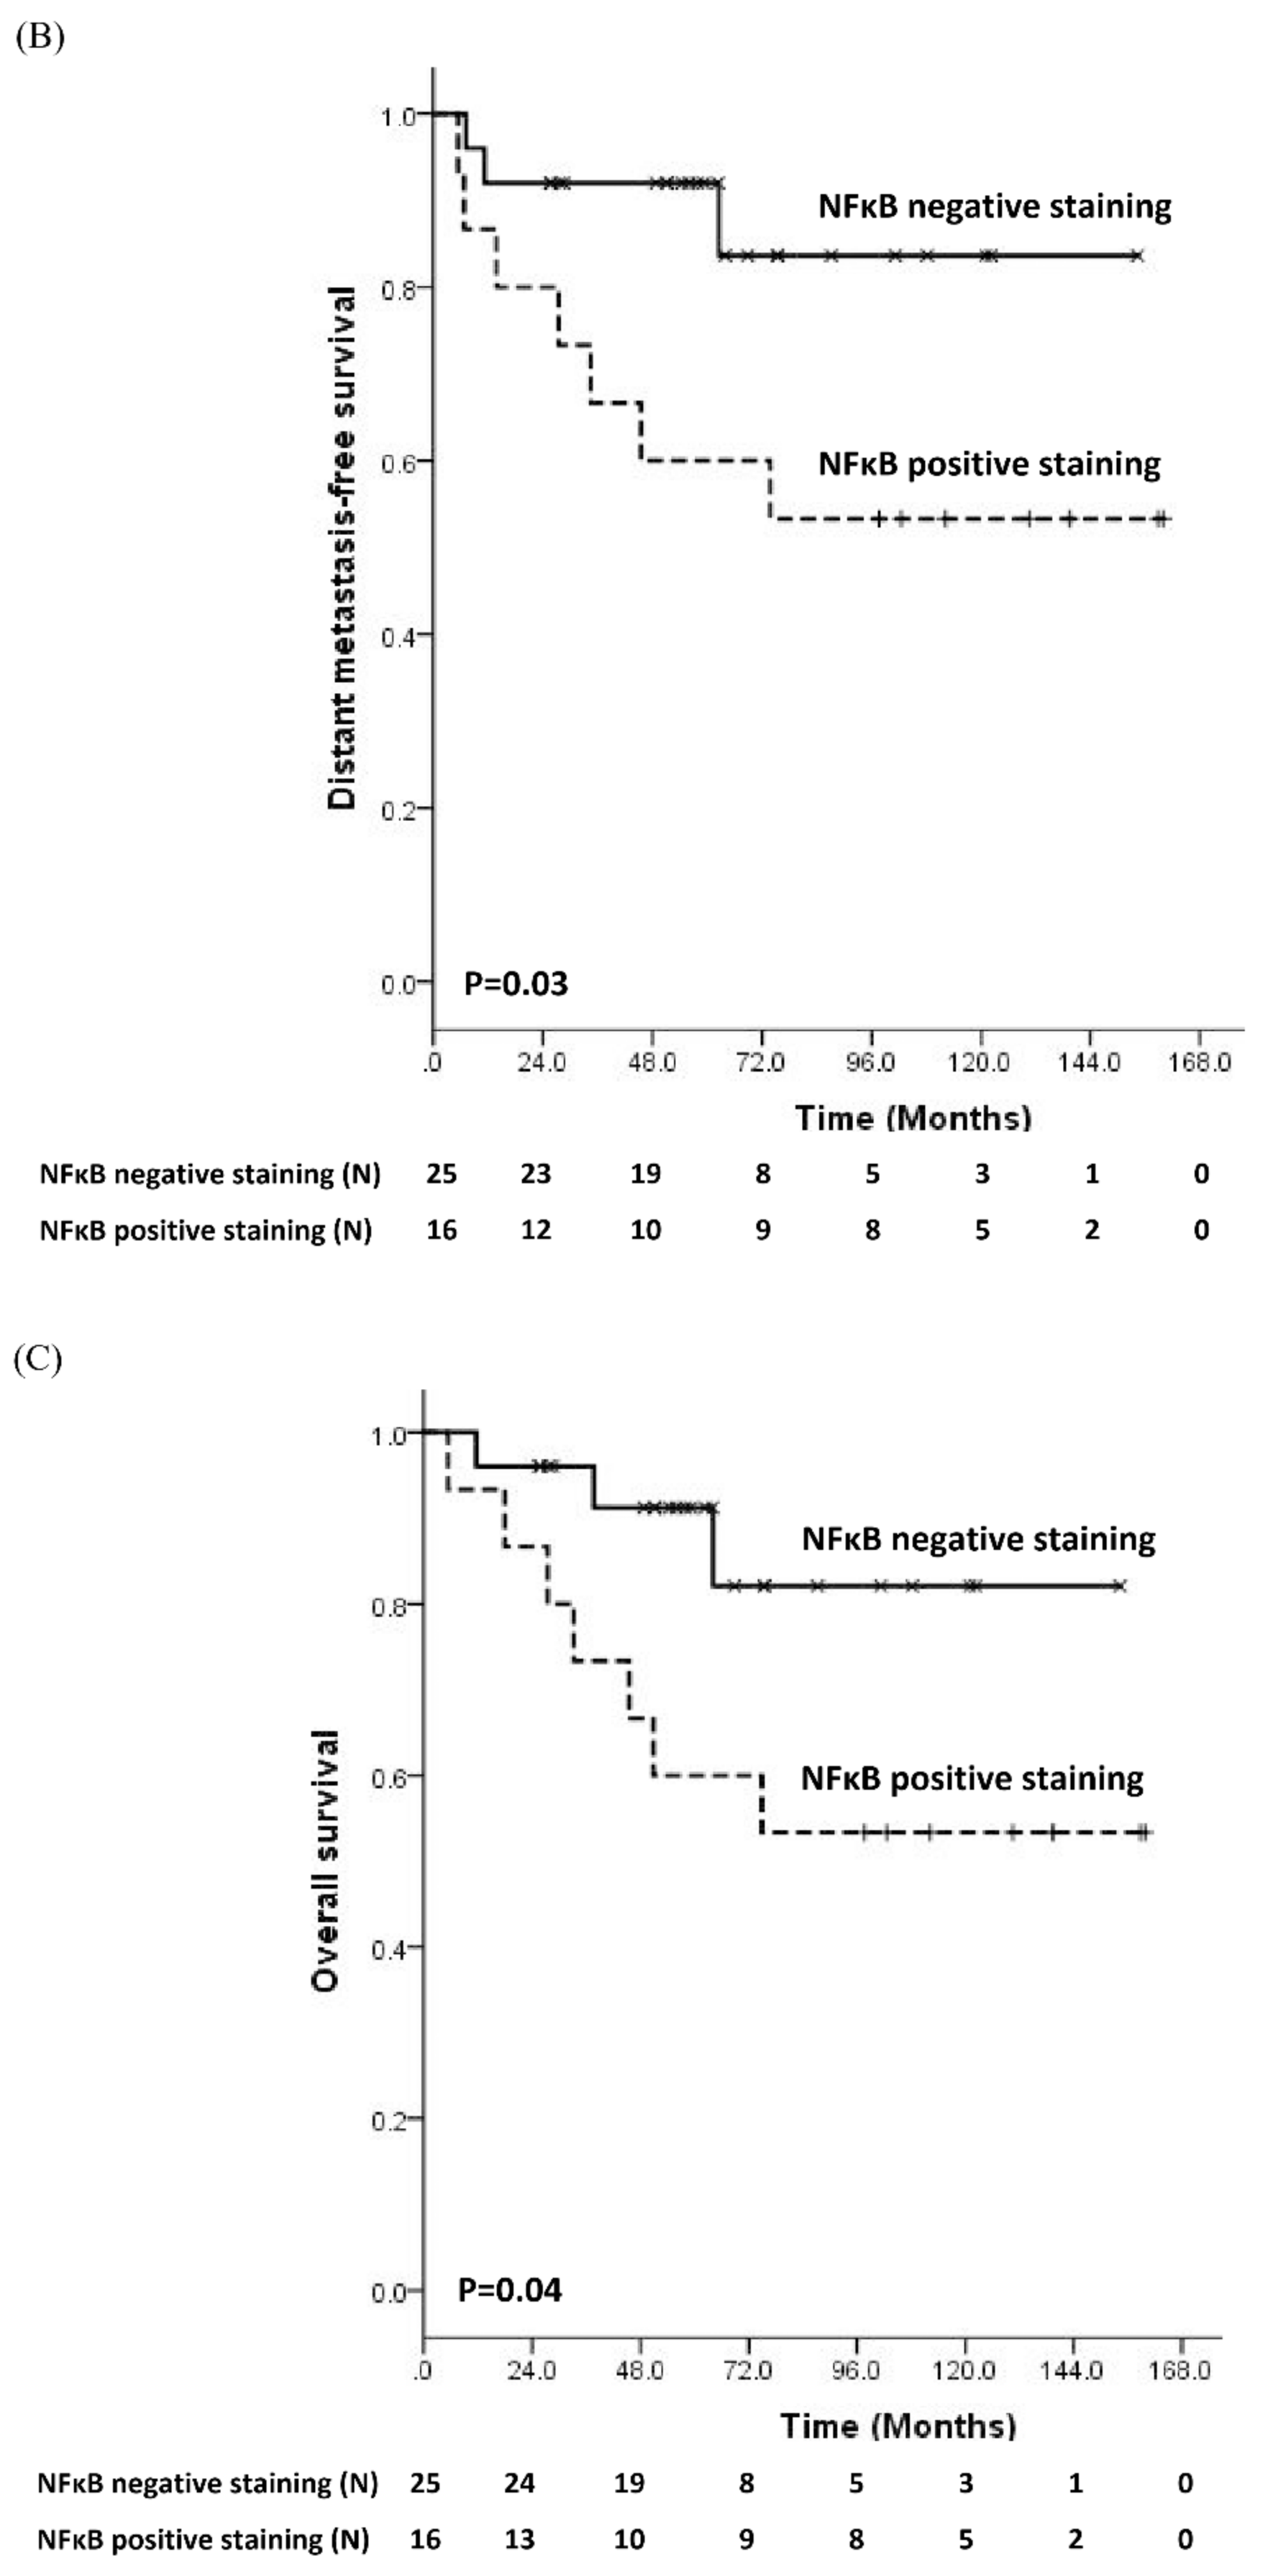

3.2. Prognostic Significance of Molecular Biomarker

3.3. Comparisons of Immunostaining of NFκB between Pre-Treatment Samples and Recurrent Samples